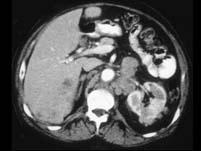

问题 男,54岁,左侧腰痛,伴间歇性血尿2个月余,请结合图像,下列哪项描述正确 ( )

选项 A、左肾转移癌 B、腹主动脉旁及左肾门区淋巴结转移 C、肝内多发转移癌 D、肝癌 E、左侧肾癌

答案 BCE